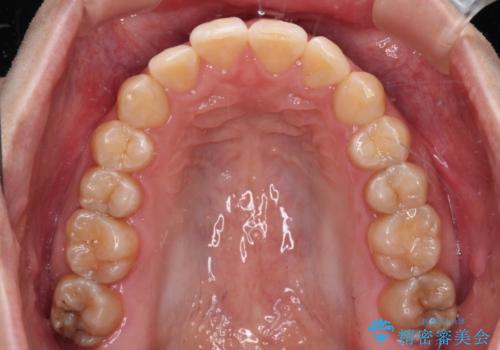

前歯のデコボコをインビザライン矯正で綺麗に改善

- 上下前歯のデコボコを気にして来院された患者様です。

全体的に叢生は軽度であったため、インビザラインにて矯正治療を行うこととしました。

舌の突出癖改善がうまくいかず、途中で舌小帯の切除を行いました。

気になる段差を納得いくまで改善させたため、治療期間は長くなりましたが、綺麗な仕上がりとなりました。